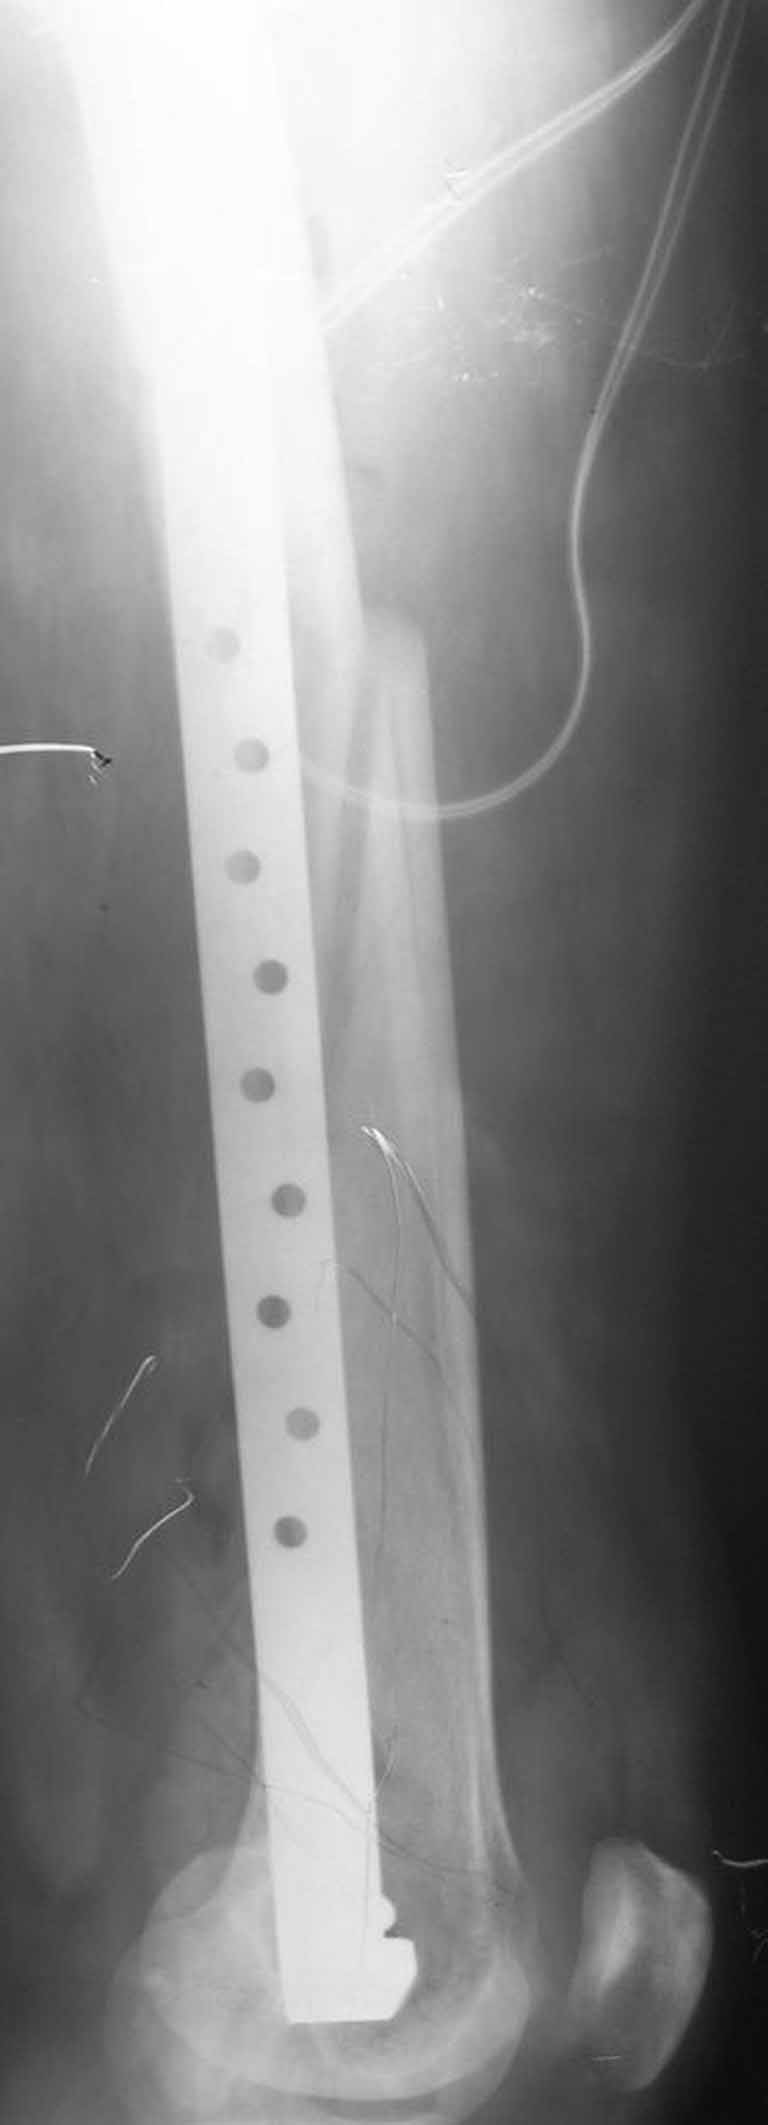

В приложении - недавний перипротезный перелом.

Методичка по закрытому интрамедулярному остеосинтезу при дистальных переломах бедра тут.